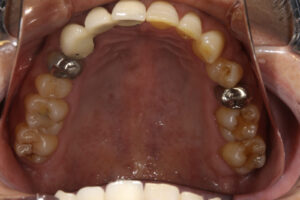

- アングルクラスⅠであった。

- アングルクラスⅠで上下顎臼歯部に不適合な修復・補綴が見られ、

- クリーニングの後、上下顎臼歯部にセラミックインレー・アンレー・インプラントを装着した。